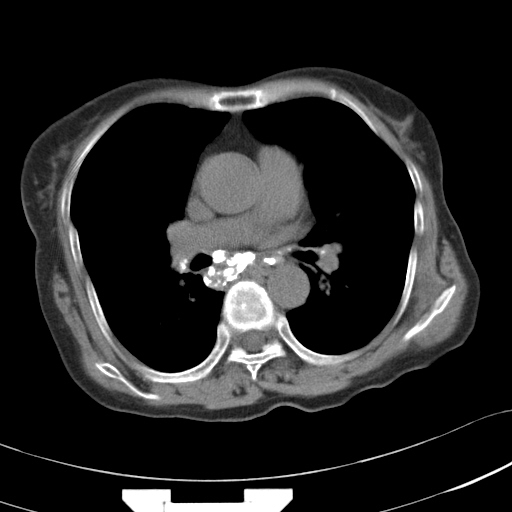

以下是引用hhcckk在2007-3-2 14:51:00的发言:[br]考虑结核球可能性大,依据[br]1病灶在下叶背段,结核的好发部位[br]2病灶内有大量的钙化,纵隔内有大量的淋巴结钙化[br]3重要的是半年前与现在相比无变化,假如是肿瘤的话不会这么‘善良’[br]4病灶周围卫星灶不明显,病灶有毛刺,胸膜凹陷,肿瘤不能完全排除,有条件的话最好做个活检

以下是引用liuyue在2007-3-2 17:15:00的发言:[br]1位置:右上叶后段[br]2性质:大分叶、粗长毛刺、条状斑片状钙化、纵隔多发淋巴结钙化,无强化,故考虑:肺结核灶(陈旧)